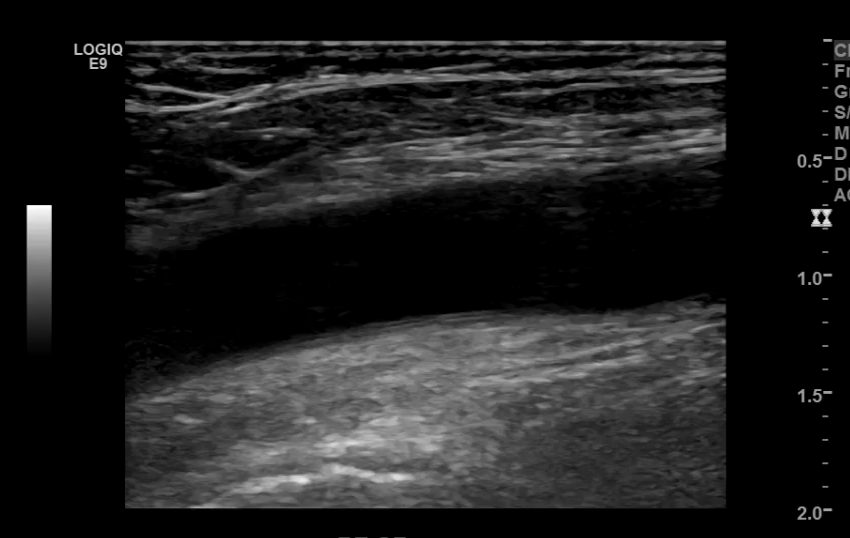

The iliac arteries bifurcate into external and internal iliac arteries (EIA and IIA). The EIA continues caudally turning into the common femoral artery (CFA) which further bifurcates into superficial femoral (SFA) and deep femoral artery (aka profunda femoris). The SFA then converts into the popliteal artery which bifurcates into the tibioperoneal trunk and anterior tibial artery (ATA). The tibioperoneal trunk bifurcates into posterior tibial artery (PTA) and the peroneal artery. The anterior tibial artery descends further to become the dorsalis pedis artery (DPA).

CFA and its branches